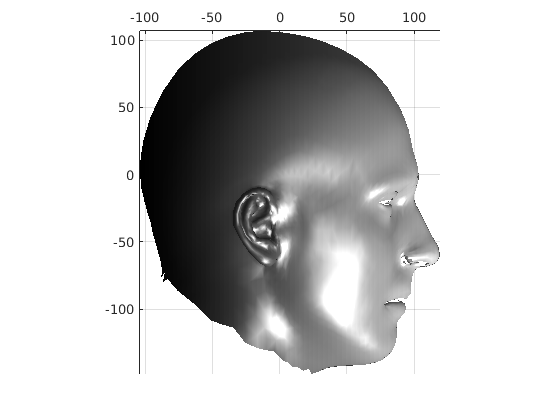

Fig. 9 shows examples of the fitted model (trained on FRGC data) on the first four subjects in our Headspace training set. Note that the mean of the landmarks in the sparse model is centred on the orgin, and so the scan data is moved towards that and becomes frontal in pose. We note that other researchers [28] have used 3D landmark localisation to find the head, but often this only includes landmarks that are relatively easy to localise, namely inner eye corners and nose. Localising more landmarks over a wider facial area has a number of advantage in terms of cropping, pose normalisation and global 3D template warping, all of which are described later.

Following this, OSNR ICP iterates over a set of decreasing mesh stiffnesses (typically 10), until the registration between the template and the scan is below some error or a maximum number of iterations is reached. Figure 28 shows a selection of template warp results. The template appears to be accurately warped onto the scan, at least in the normal direction of the surfaces, it is not possible to see error tangential to the surface. Furthermore, we have noted errors on some scans on the ears. To improve these we need a method of automatically landmarking the ears, which is an area for further work.

The first two modes of head variation are shown in figures 29 and 30. These include the cranial height / facial angle mode and the (almost) pure size mode, as seen in the sagittal profile model.